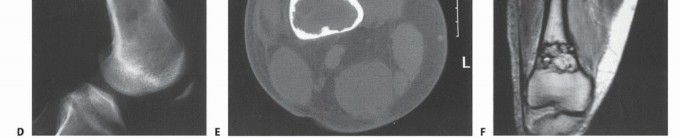

Imaging Set 1: Pathophysiology and Staging Fundamentals

- Plain Radiography: The cornerstone of initial evaluation. It accurately predicts the diagnosis in over 80% of extremity bone tumors. It defines the lesion's location, zone of transition (narrow/sclerotic = benign/slow; wide/permeative = malignant/aggressive), cortical destruction, and periosteal reactions (Codman triangle, onion-skinning, sunburst pattern).

- Computed Tomography (CT): The modality of choice for assessing fine osseous detail, cortical integrity, and matrix mineralization. Thin-slice (≤1 mm) helical CT allows for precise 3D reconstructions. Intravenous contrast is essential to delineate the relationship of the soft tissue mass to major vascular bundles. Chest CT is mandatory for staging to rule out pulmonary metastases.

- Magnetic Resonance Imaging (MRI): The gold standard for evaluating the local extent of the tumor. It accurately defines the intramedullary extent (allowing calculation of bone resection levels), soft tissue extension, joint involvement, and the presence of skip metastases. T1-weighted images best define marrow replacement; T2-weighted and STIR sequences highlight peritumoral edema and the soft tissue mass. Contrast enhancement differentiates cystic from solid components and clarifies neurovascular proximity.